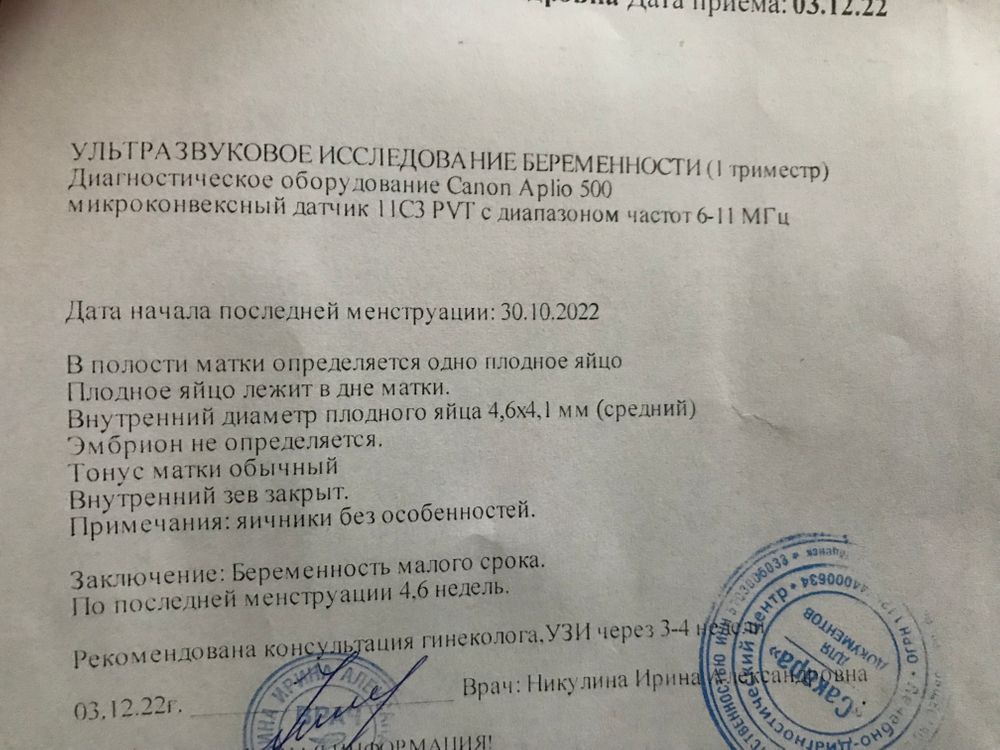

Здравствуйте девочки. Я в расстроенных чувствах. Только сегодня утром сходила на узи, обрадовалась, диагностировали маточную беременность. Узист говорил «хорошая беременность, все замечательно». И буквально через 1,5 часа начались спазмы и колол низ живота. Пошла кровь - коричневого цвета… побежала в приемный покой. Положили. Укололи кровоостанавливающее, противовоспалительное. Дали праджисан пить по 1 таблетке на ночь! Боюсь…что там с моим малышом в результате будет 🙈 узи сказали, только в понедельник.